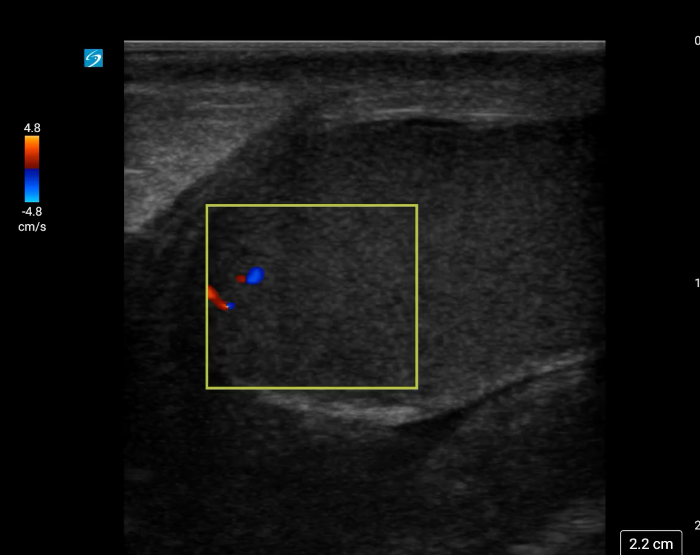

[Torsion - image 2.pngImage 2. Twisted spermatic cord (“corkscrew sign”) concerning for testicular torsion.

In your first image (Image 1), you realize there is no flow with color Doppler. Additionally, you find a torsed cord complex (Image 2), also known as the “corkscrew sign.” You consult Urology who is busy in the operating room with another case. You decide to perform a manual detorsion due to your concern for testicular atrophy and risk of infertility. Using the open book technique, you get relief of pain and return of vertical positioning of the testicle after two rotations. On your repeat testicular POCUS with color Doppler you obtain these images (Images 3 and 4), which demonstrate venous and arterial flow throughout the testicle. The cord is now untwisted and appears linear in orientation.

Torsion - image 4_crop.pngImage 4. Linear, untwisted appearance of the spermatic cord with accompanying vessels.